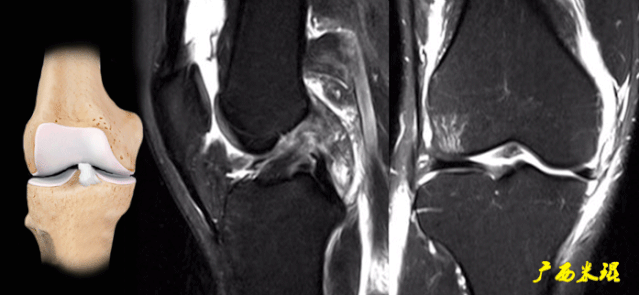

(八)ACL损伤间接征象:

1)ACL撕裂后胫骨前移位出现的一系列改变

2)骨挫伤:

一旦ACL撕裂,胫骨就相对于股骨前移,使股骨外侧髁和胫骨外后方撞击,双方均出现水肿,而且膝关节屈曲的程度决定股骨髁挫伤的部位。

3)沟槽征:

当股骨外髁骨因撞击造成的凹陷深度>2mm时称为沟槽征,代表受到撞击的暴力更大。

6)胫骨前移:

胫骨后缘垂直线位于股骨髁后缘垂直线前方5mm以上。

由于MRI检查时病人为平卧位,胫骨应该因重力而后沉,因此胫骨前移征往往暗示膝关节处于交锁状态。

7)外侧半月板后角裸露征:

外侧半月板后角后缘垂直线位于胫骨后缘皮质垂直线之后方。